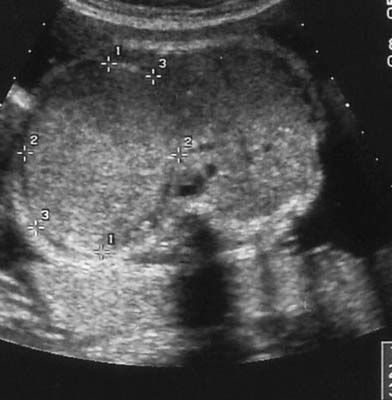

Tumeur de Wilms